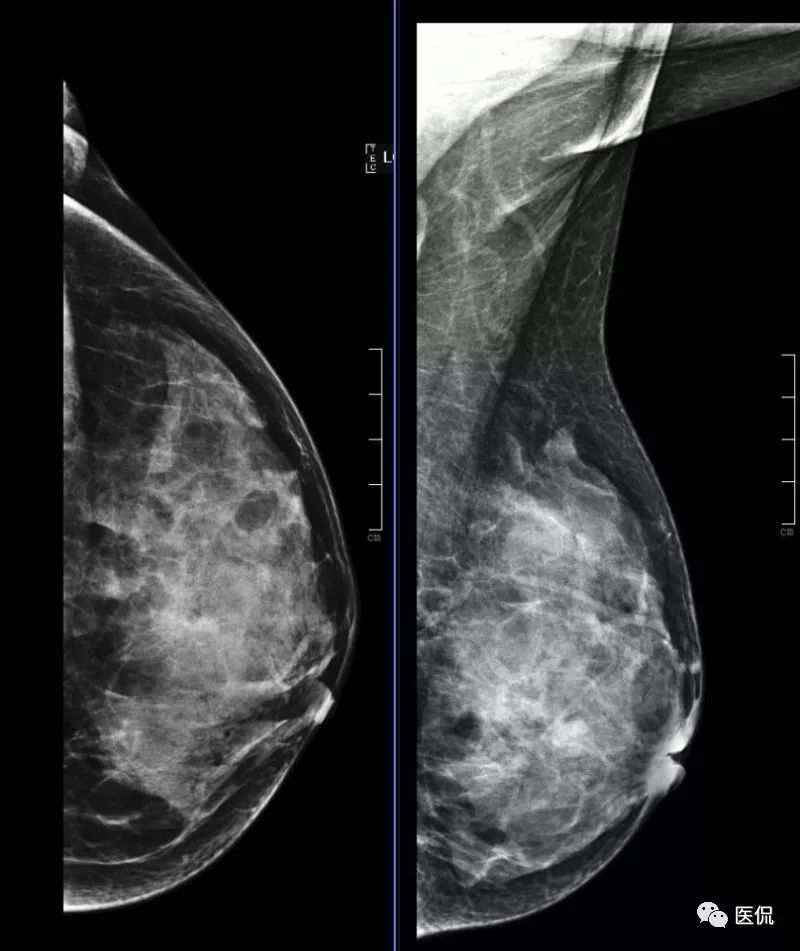

CT/MR扫描X鉬靶检查:

X线钼靶检查设备型号为Selenia Dimensions乳腺X射线摄影系统。包括双乳内外侧斜位(MLO)及头尾位(CC)。

本病例特点为年轻女性,以发现左乳肿块1+月就诊,病程较短,有先天性乳头内陷。X钼靶显示左乳外下象限腺体结构紊乱,密度增高,边缘模糊,无钙化,腋窝无增大淋巴结。超声显示病灶范围较为广泛,为混杂低回声区,边缘不清。MRI显示病灶呈片状稍长T2信号,边缘不清,DWI(b=600)为稍高信号,增强后明显不均质强化,时间-信号曲线为平台型。上述影像表现均提示病变范围广泛,边界模糊不清,无肿块显示,结合患者先天性左乳头凹陷,有乳腺炎发病基础,因此在诊断上首先需要考虑浆细胞性乳腺炎的可能性。

乳腺X线摄影是基本检查方法,主要表现为患侧乳腺的大片密度增高,边缘不清,有时可在病灶区域内看到迂曲透亮的扩张导管影。超声可清晰显示扩张的导管,浆细胞性乳腺炎一般分为三型:(1)包块型,肿块多位于乳晕附近,边界不清,形态不规则,与乳腺癌不易鉴别;(2)单纯导管扩张型:乳腺腺体内见多发扩张导管,内透声差;(3)脓肿形成型:范围较广泛,边界模糊,脓肿形成后深压探头可显示脓液流动,光点漂浮。MRI检查具有较好的组织分辨率及空间分辨率,能从多个角度显示病灶的信号、形态特点,T1WI呈等低信号,压脂T2WI呈高信号,动态增强呈不均匀明显强化,脓肿形成后脓肿壁环形强化,DWI脓腔呈明显高信号,时间-信号强度曲线多为I型或II型。对与乳腺癌鉴别具有较大意义。